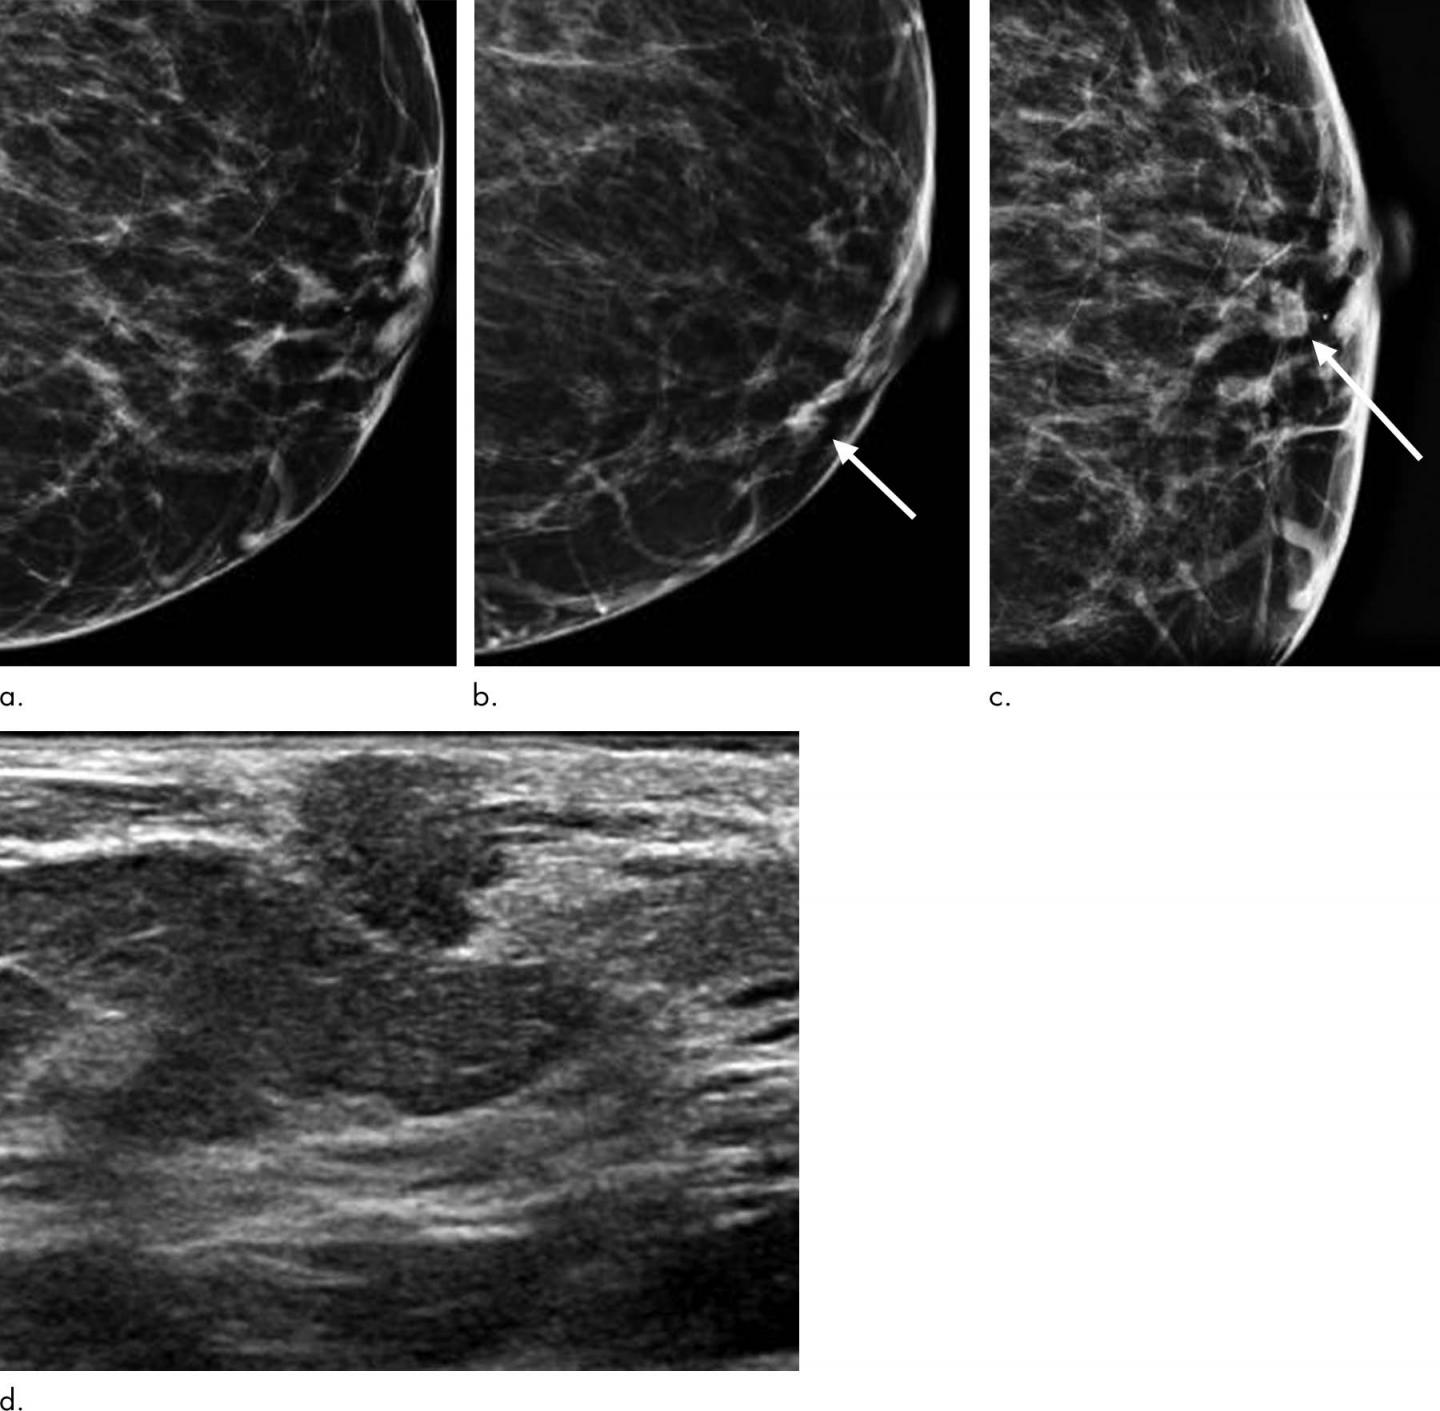

image: Images show symptomatic false-negative cancer in a 73-year-old black woman who presented with a palpable abnormality 64 days after negative screening mammography. (a) Negative screening left digital breast tomosynthesis (DBT) mammogram. (b) Diagnostic DBT mammogram shows a new palpable mass (arrow). (c) Spot-compression DBT mammogram enables confirmation of mass (arrow). (d) Ultrasound (US) image shows hypoechoic mass with angular margins. Subsequent US-guided biopsy revealed estrogen receptor- and progesterone receptor-positive and human epidermal growth factor receptor 2-negative invasive ductal carcinoma.